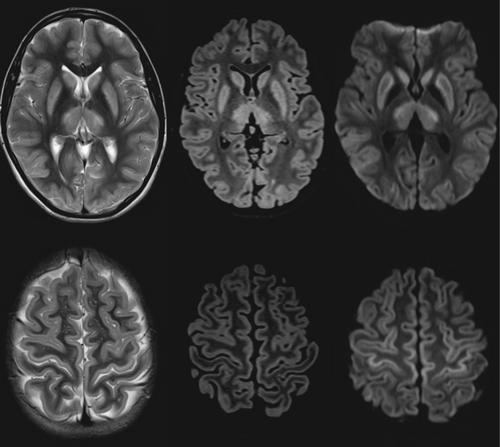

本病例报告强调了一个不典型的Canavan病(CD)的表现,在13岁的女性有意震颤和精细运动困难。神经影像学显示大脑各区域的对称变化,初步提示神经代谢或线粒体紊乱。然而,进一步的研究,包括生化分析和全基因组测序,证实了CD的诊断。与经典表现不同,本病例表现出较轻的症状和不寻常的MRI表现,有助于扩大CD的临床和放射谱。强调识别这种非典型表现对于CD的准确诊断和治疗的重要性。

This case report highlights an atypical presentation of Canavan disease (CD) in a 13-year-old female with intention tremor and fine motor difficulties. Neuroimaging revealed symmetrical changes in various brain regions initially suggesting a neurometabolic or mitochondrial disorder. However, further investigations, including biochemical analysis and whole genome sequencing, confirmed a diagnosis of CD. Unlike classical presentations, this case exhibited milder symptoms and unusual MRI findings, contributing to the expanding clinical and radiological spectrum of CD. The importance of recognizing such atypical presentations is emphasized for accurate diagnosis and management of CD.